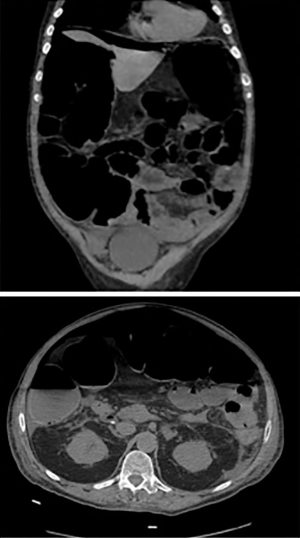

On postoperative day 5, the patient suddenly experienced an acute exacerbation of abdominal pain. An upright abdominal radiograph (Figure 3) demonstrated findings consistent with free air under the diaphragm. A computed tomography scan of the abdomen (Figure 4) demonstrated pneumoperitoneum and dilation of the large and small bowel extending to the splenic flexure. Of note, there was no apparent orthopaedic implant complications or suspicion of mechanical obstruction. He was started on antibiotics and was taken to the operating room by general surgery for an exploratory laparotomy. Intra-operative findings were significant for multiple abdominal adhesions and multiple pinhole sized perforations at the splenic flexure and cecum. Suture repair of all perforations and an adhesiolysis was performed. A nasogastric tube was placed at the end of surgery.